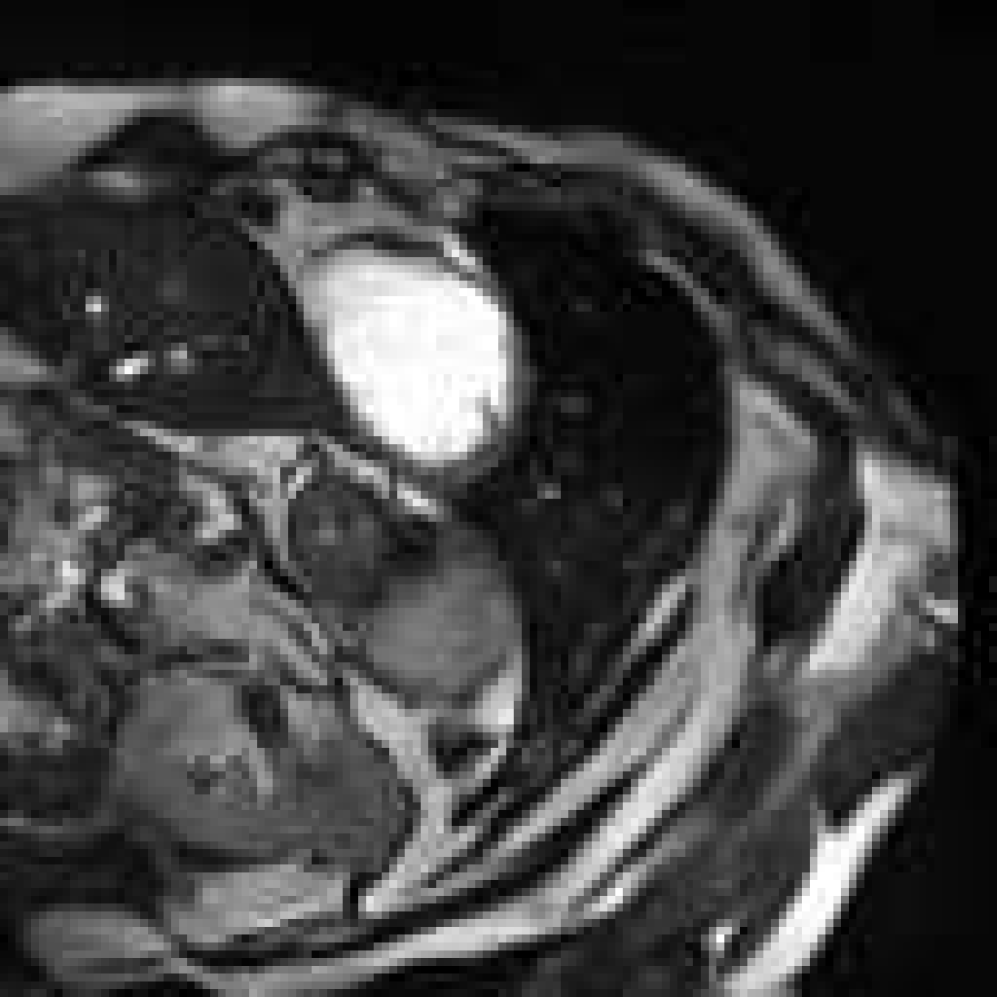

Figure 4: Image synthesis using various τ\tau and diffusion range NN with fixed D=4D=4. Since τ\tau controls the step size of guidance, a very small τ\tau results in no guidance.

Figure 5: Controlling structural consistency by extremal settings of DD and τ\tau. All images are synthesised using the same reference (indicated with a yellow arrow in Fig.  4). From left to right: (D=16D=16, τ=1\tau=1), (D=32D=32, τ=1\tau=1), (D=1D=1, τ=18\tau=18), and (D=1D=1, τ=24\tau=24). Large DD induces semantic drift; high τ\tau leads to more preservation of the reference anatomy.

Synthetic cardiac MR images (Fig. 4 and Fig. 4) closely resembled their respective reference image with good reconstruction on the three important regions of interest (LV, RV, MYO). With different refinement scale for image adaptation, the cardiac MR images had different level of reconstruction, highlighting a controllable trade-off between introducing novel synthetic structures and preserving reference anatomy (Fig. 5). Visual assessment revealed occasional white artifacts in the background of the generated images, likely caused by residual noise retained during the reverse process. Nevertheless, the overall anatomical structures remained well-preserved, even in the presence of a limited dataset. While diffusion models are traditionally considered data-hungry, our results suggest that structural fidelity can be maintained with constrained data availability.